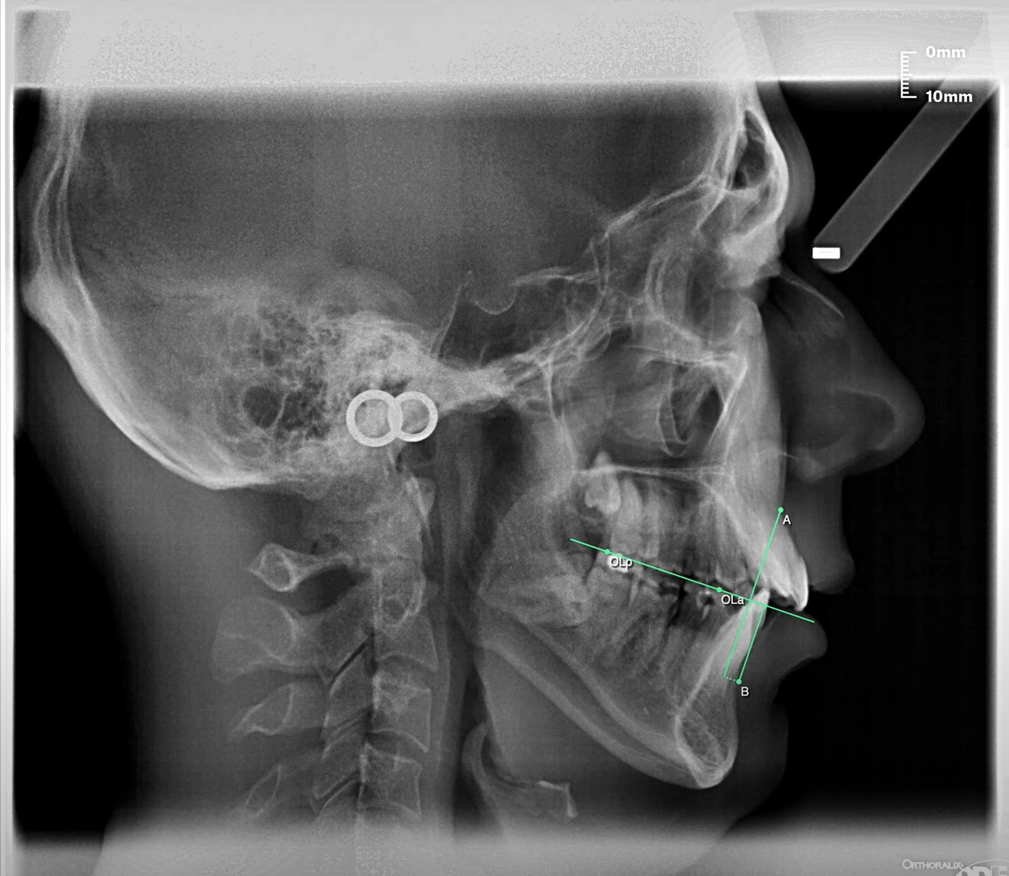

The extent of jaw disharmony is measured through the anteroposterior jaw relationship. Perpendicular lines are drawn from points A and B upto the occlusal plane of which points of intersection are noted as AO and BO respectively. For the average normal AO to BO in males is 1mm while 0 in females with BO being posterior to AO. In skeletal Class II malocclusion, BO is located more posteriorly to AO with a distance greater than 1mm. While in skeletal Class III cases, BO is located anterior to AO with a negative measurement.

Dr. Jacobson pointed out that the severity of anteroposterior jaw dysplasia is appropriately measured through the maxillomandibular relationship rather than using cranial or extracranial landmarks. The occlusal plane, which is common to both upper and lower jaws is the most appropriate reference plane to relate both jaws. When the occlusal plane is used, the relative direction of growth in relation to cranial or extracranial reference planes becomes irrelevant to the overall assessment of the severity of jaw disharmony.